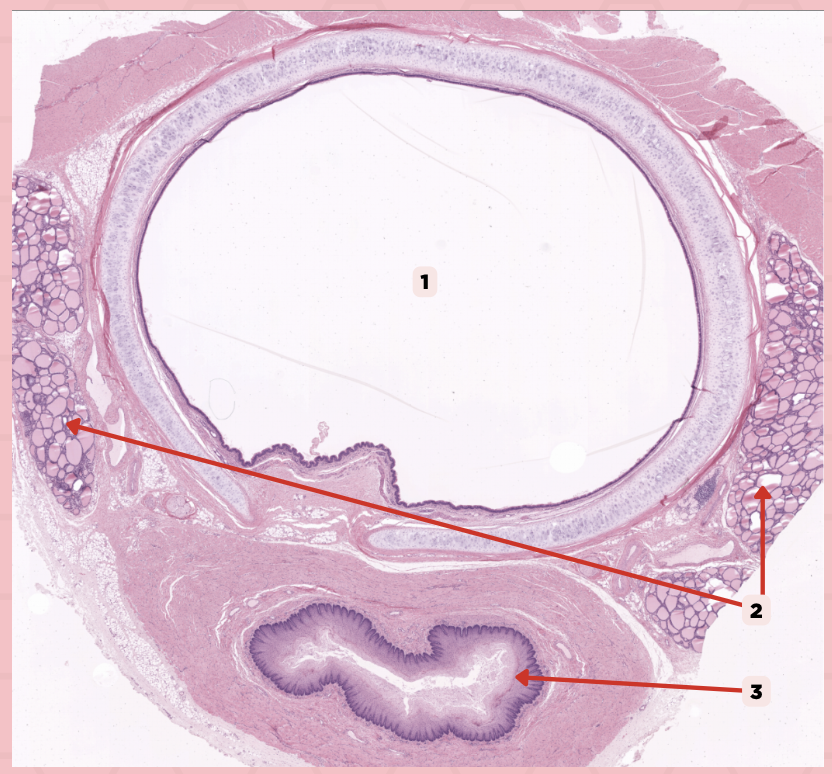

Lumen

It is a large ovoid space that occupies the center of the trachea.

Thyroid gland

This consist of cystic structures that contain highly eosinophilic material on either side of the trachea.

Lumen

Identify the structure labeled as 1.

Thyroid Gland

Identify the structure labeled as 2.

Esophagus

Identify the structure labeled as 3.

Ciliated Pseudostratified Columnar Epithelium

What is the epithelium of no. 3?

MALT

What type of lymphoid tissue supplies no. 3?